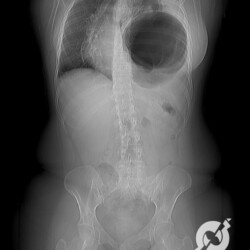

Muitas vezes olhamos uma radiografia de abdome apenas no que corresponde á cavidade peritoneal. Mas não podemos esquecer que podemos obter muitas informações nas estruturas extracavitárias. Aqui podemos identificar um grande abaulamento inguinal à esquerda com gás de permeio, que corresponde a uma volumosa hérnia inguinoescrotal com insinuação de alças intestinais.